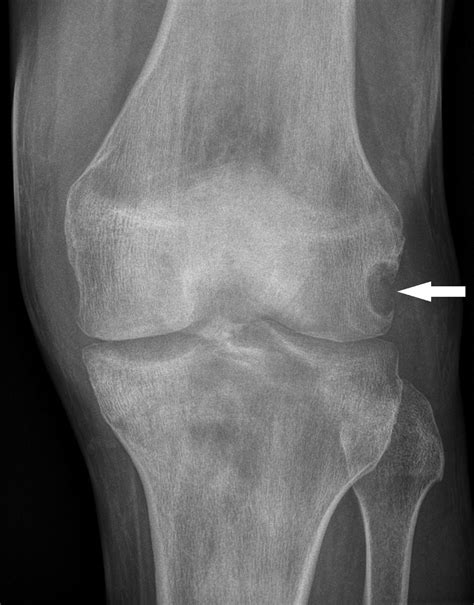

• gout in knee xray